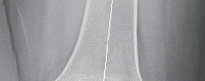

P ITFALLS Wide, osteopenic IM canals often require cemented fixation. Uncemented stems must be long enough to …